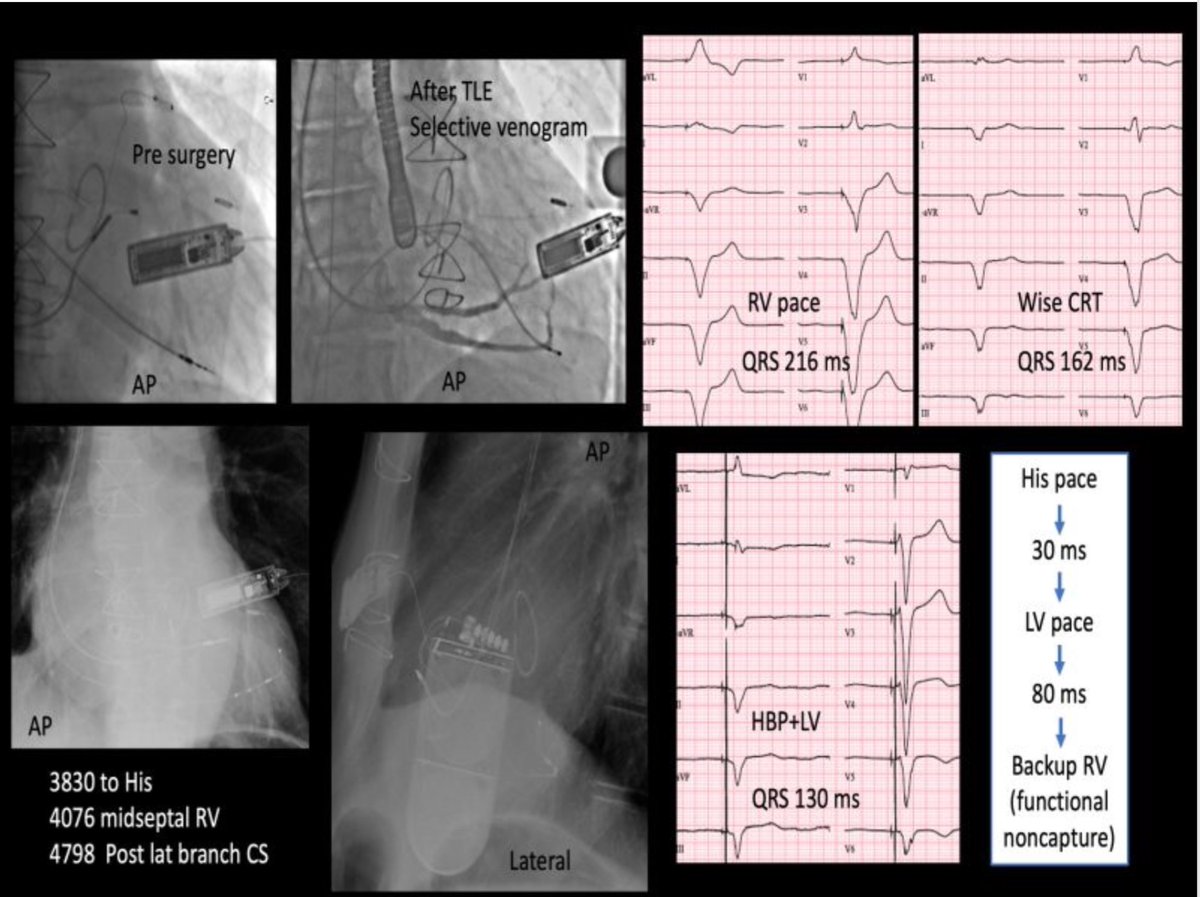

#EPeeps 75yr male, DCM, LBBB, Chronic AF, AVN ablated. Two previous suboptimal LV leads w exit-block, Wise-CRT impossible acoustic window in supine position. Amazing shortening of QRSd to 130ms with HBP+ postlat LV, after extraction of previous 4 leads. Case done w/ Dr. Mörtsell.